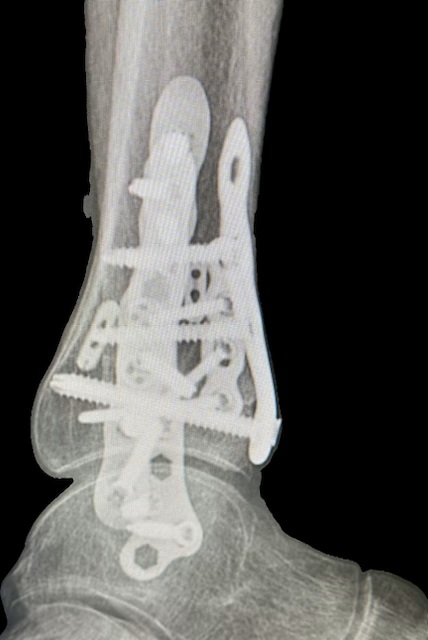

Last summer, despite strong winds and my better judgment, I headed out to water ski. The lake and the slalom course were calling. I missed a turn and CRASHED hard - likely hitting the water at around 50 mph and flipped head over heels three or four times. My hard-shell boot didn’t release. When I finally stopped, I had suffered a devastating trimalleolar ankle fracture: multiple breaks involving the lateral, medial, and posterior malleolus, with displacement and widening of the lateral mortise. Basically, I broke my ankle with every body roll until I came to a stop. The pain was unbelievable.

From the first consultation, Dr. Cody helped me understand the severity of the injury and what it would take to recover. She outlined a detailed plan and scheduled surgery for the following week. I’ll never forget that day - August 21st - when she rebuilt my ankle using 21 screws, four plates, mesh, and cadaver grafts. It was an extraordinary procedure performed by an extraordinary surgeon.

By October 31st, I was back at work but the flex and mobility in my ankle was stiff and limited. On March 21st - about 8 months from ankle fracture - Dr. Cody removed all the hardware - a huge step forward. From there, my progress accelerated. Skyrocketed!